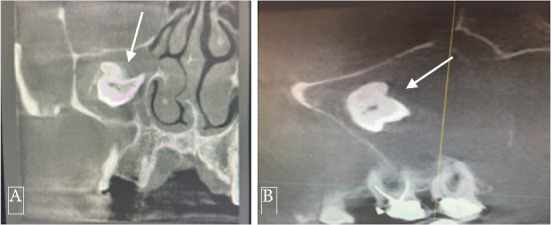

恒磨牙异位萌出是一种罕见的发育异常,其特征是牙位异常,可导致严重的并发症。在罕见的情况下,异位磨牙可能与含牙囊肿有关,特别是在上颌窦内,对诊断和治疗提出了挑战。本文报告一位58岁男性病患,表现为慢性右上颌鼻窦炎、间歇性面部疼痛及脓性鼻及口腔分泌物。放射学评估,包括锥束计算机断层扫描(CBCT),显示一个完全不透明的右上颌窦包含一个异位上颌磨牙。此外,发现一个与含牙囊肿一致的大囊性病变,占据整个窦腔。手术在全麻下采用Caldwell-Luc入路。这包括在上颌前壁制造一个骨窗,以方便切除异位牙和相关的囊性病变。组织病理学检查证实有牙性囊肿,表现为慢性炎症浸润和纤维化。上颌窦的异位磨牙通常无症状,但可表现为反复的鼻窦炎、疼痛和口窦沟通。存在一个大的含牙囊肿增加并发症的风险,并可能模糊放射学解释由于窦混浊。该病例强调了综合影像学检查和早期手术干预的必要性,以防止长期并发症。意识到这种罕见的情况可以帮助临床医生及时诊断和适当的管理,最终保留鼻窦功能,并尽量减少进一步的问题。

Ectopic eruption of permanent molars is an uncommon developmental anomaly characterized by abnormal tooth positioning, which can lead to significant complications. In rare instances, ectopic molars may be associated with dentigerous cysts, particularly within the maxillary sinus, posing challenges for diagnosis and management. This report discusses a rare case of a 58-year-old male who presented with chronic right maxillary sinusitis, intermittent facial pain, and purulent nasal and oral discharge. Radiological evaluation, including cone beam computed tomography (CBCT), revealed a completely opacified right maxillary sinus containing an ectopic maxillary molar. Additionally, a large cystic lesion consistent with a dentigerous cyst was found, occupying the entire sinus cavity. Surgical management was performed using the Caldwell-Luc approach under general anesthesia. This involved creating a bone window in the anterior maxillary wall to facilitate the removal of the ectopic tooth and the associated cystic lesion. Histopathological examination confirmed the presence of a dentigerous cyst exhibiting chronic inflammatory infiltration and fibrosis. Ectopic molars in the maxillary sinus are often asymptomatic but can present with recurrent sinusitis, pain, and oroantral communication. The existence of a large dentigerous cyst heightens the risk of complications and may obscure radiological interpretation due to sinus opacification. This case highlights the necessity of comprehensive imaging and early surgical intervention to prevent long-term complications. Awareness of such rare conditions can help clinicians in prompt diagnosis and appropriate management, ultimately preserving sinus function and minimizing further issues.